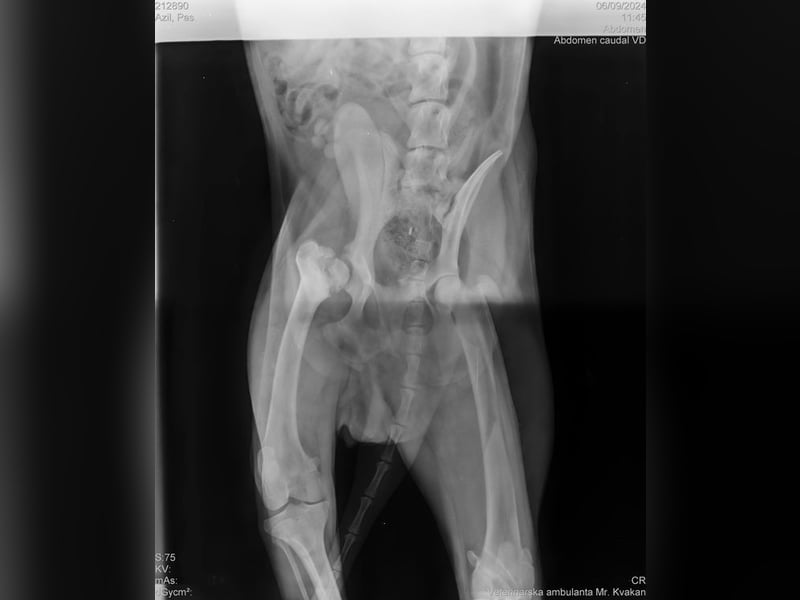

Wir durften ihn deshalb ohne Probleme mit ins Tierheim nehmen, da Yondu Probleme mit der Hüfte und ein etwas kürzeres Beinchen hat. Youdu hat bei einen Besuch beim Tierarzt entsprechende Röntgenbilder von Hüfte und Hinterbeinchen, die den Interessierten in der Bildergalerie zur Verfügung gestellt werden.